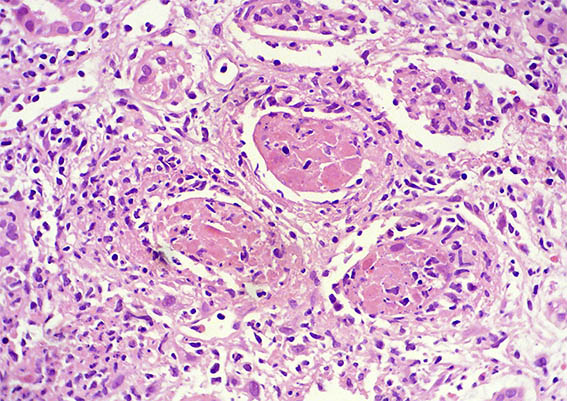

The patient is a 32-year-old man, kidney transplanted 18 months ago due to end-stage renal disease of unknown cause. A cellular rejection episode was evidenced in the first year. Good kidney function in the last control (16 post-transplantation months). Now in a new control the serum creatinine has risen to 1.9 mg/dL. Mild proteinuria and microscopic hematuria, no other abnormalities.

See the images of the renal allograft biopsy.

Figure 3. H&E, X400.